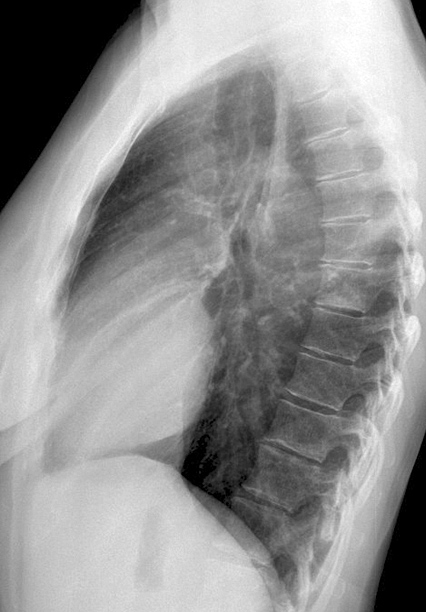

Fat Pad

Case 3b